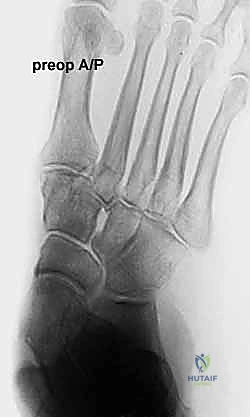

* الأشعة السينية (X-rays) مع تحمل الوزن: ضرورية لتقييم درجة انهيار القوس وزوايا العظام (مثل زاوية تالونافيكولار Meary's Angle).